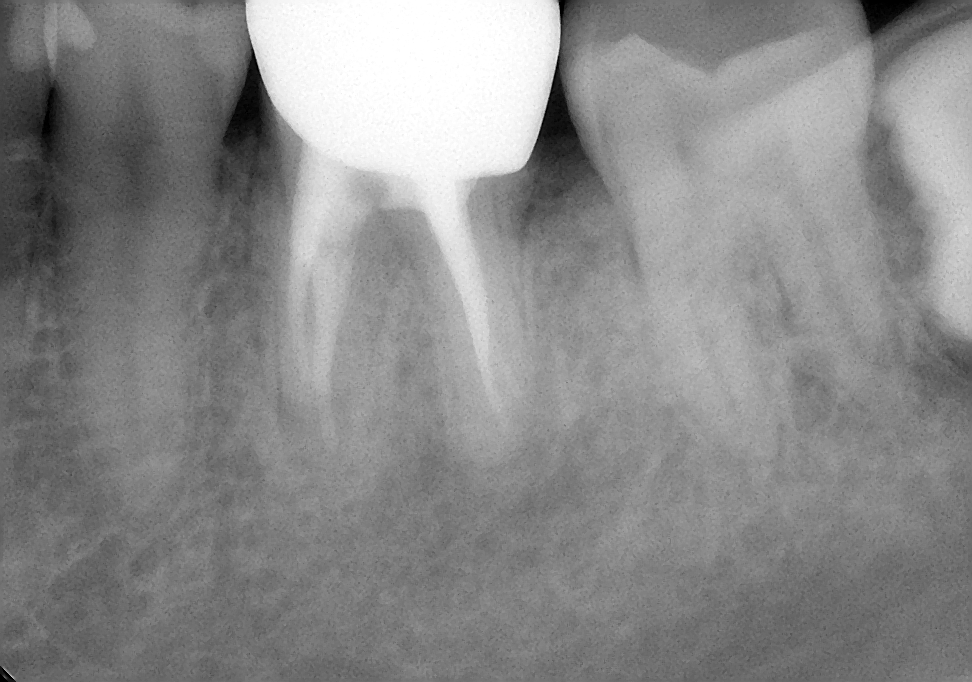

今回の患者様は、もうかれこれ10年の長いお付き合いの患者様です。来院のきっかけは、むし歯の治療でしたが、レントゲン写真から以前の神経を取った治療を行ったところに新たな病気が出来ていました。患者様の希望もあり、根管治療とその後の被せ物の治療も行いました。

約10年前のその当時を思い出してみると、私はマイクロスコープを使った根管治療を始めたばかりの頃だったと思います。いろいろなセミナーに通い、技術を習得していました。

その習得したばかりの技術を用いして何とかこの歯を保存できないかとがんばっていたことと思われます。

現在と比べると、使用している器具や材料では違いはありますが、治療において守るべき基本的なところは変わっておらず、基本に忠実な治療をしたのではないでしょうか。